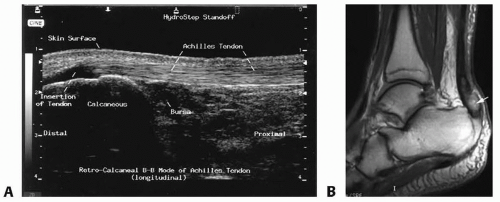

Ultrasound is a useful first-line imaging technique, with sensitivity of 100% (FIG 2A).

Ultrasound tendon gap greater than 4 mm with patient in equinus (plantar flexion) indicates the need for surgical repair.

Ultrasound can differentiate partial vs complete tear:

This is more difficult with a tear at the proximal musculotendinous junction, in which sensitivity is much lower.

MRI is the best imaging modality for Achilles tendon rupture, with sensitivity of 100% (FIG 2B).

MRI should always be obtained if any uncertainty exists regarding location, completeness, or length of tear.